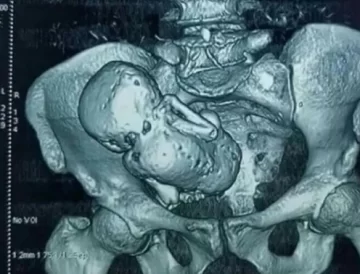

Una mujer de 84 años fue al médico por un dolor abdominal y al realizarle los estudios de rutina descubrieron que presentaba un feto momificado en su vientre que llevaba más de 40 años allí. Al parecer, la mujer jamás se había enterado que había estado embarazada.

Se trataría de un embarazo ectópico que se momificó, el feto tenía 40 semanas de gestación, pero nunca le provocó trastornos de salud. El embarazo habría sido concebido hace cuatro décadas.

En medicina tiene el nombre de litopedia. Es un proceso que se genera cuando un óvulo fertilizado se adhiere a un lugar fuera del útero. A pesar de ello, el feto crece, pero no puede sobrevivir al no contar con el lugar y las condiciones adecuadas.